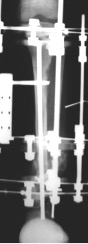

Hemostazı takiben katlar anatomik olarak kapatılmalıdır. Daha önceden hazırlanmış 3 halkadan oluşan sirküler eksternal fiksatör K-telleri ile frontal ve sagittal planlarda anatomik eksene paralel olarak yerleştirilmelidir. Burada dikkat edilmesi gereken fiksatörün K-telleri ile Steinmann çivisi temas etmemelidir. Proksimal tibia’dan fizise çok yakın kortikotomi ile mevcut kısalık da rekonstrukte edilir.